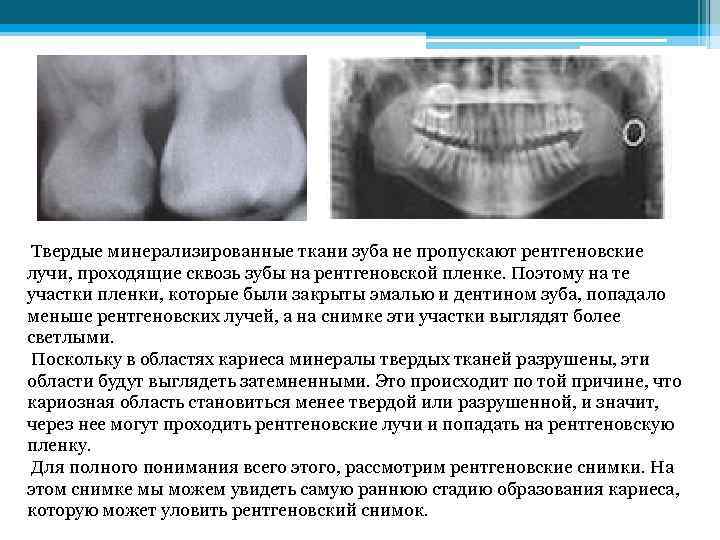

Твердые минерализированные ткани зуба не пропускают рентгеновские лучи, проходящие сквозь зубы на рентгеновской пленке. Поэтому на те участки пленки, которые были закрыты эмалью и дентином зуба, попадало меньше рентгеновских лучей, а на снимке эти участки выглядят более светлыми. Поскольку в областях кариеса минералы твердых тканей разрушены, эти области будут выглядеть затемненными. Это происходит по той причине, что кариозная область становиться менее твердой или разрушенной, и значит, через нее могут проходить рентгеновские лучи и попадать на рентгеновскую пленку. Для полного понимания всего этого, рассмотрим рентгеновские снимки. На этом снимке мы можем увидеть самую раннюю стадию образования кариеса, которую может уловить рентгеновский снимок.

Твердые минерализированные ткани зуба не пропускают рентгеновские лучи, проходящие сквозь зубы на рентгеновской пленке. Поэтому на те участки пленки, которые были закрыты эмалью и дентином зуба, попадало меньше рентгеновских лучей, а на снимке эти участки выглядят более светлыми. Поскольку в областях кариеса минералы твердых тканей разрушены, эти области будут выглядеть затемненными. Это происходит по той причине, что кариозная область становиться менее твердой или разрушенной, и значит, через нее могут проходить рентгеновские лучи и попадать на рентгеновскую пленку. Для полного понимания всего этого, рассмотрим рентгеновские снимки. На этом снимке мы можем увидеть самую раннюю стадию образования кариеса, которую может уловить рентгеновский снимок.

Стрелкой указывается затемненная область эмали зуба - это и есть начальный кариес. Это кариозное повреждение может и не развиваться дальше, если пациент будет пользоваться зубной нитью чаще и тщательнее. На этом снимке видно, что помимо эмали, дентин тоже вовлечен в процесс.

Стрелкой указывается затемненная область эмали зуба - это и есть начальный кариес. Это кариозное повреждение может и не развиваться дальше, если пациент будет пользоваться зубной нитью чаще и тщательнее. На этом снимке видно, что помимо эмали, дентин тоже вовлечен в процесс.